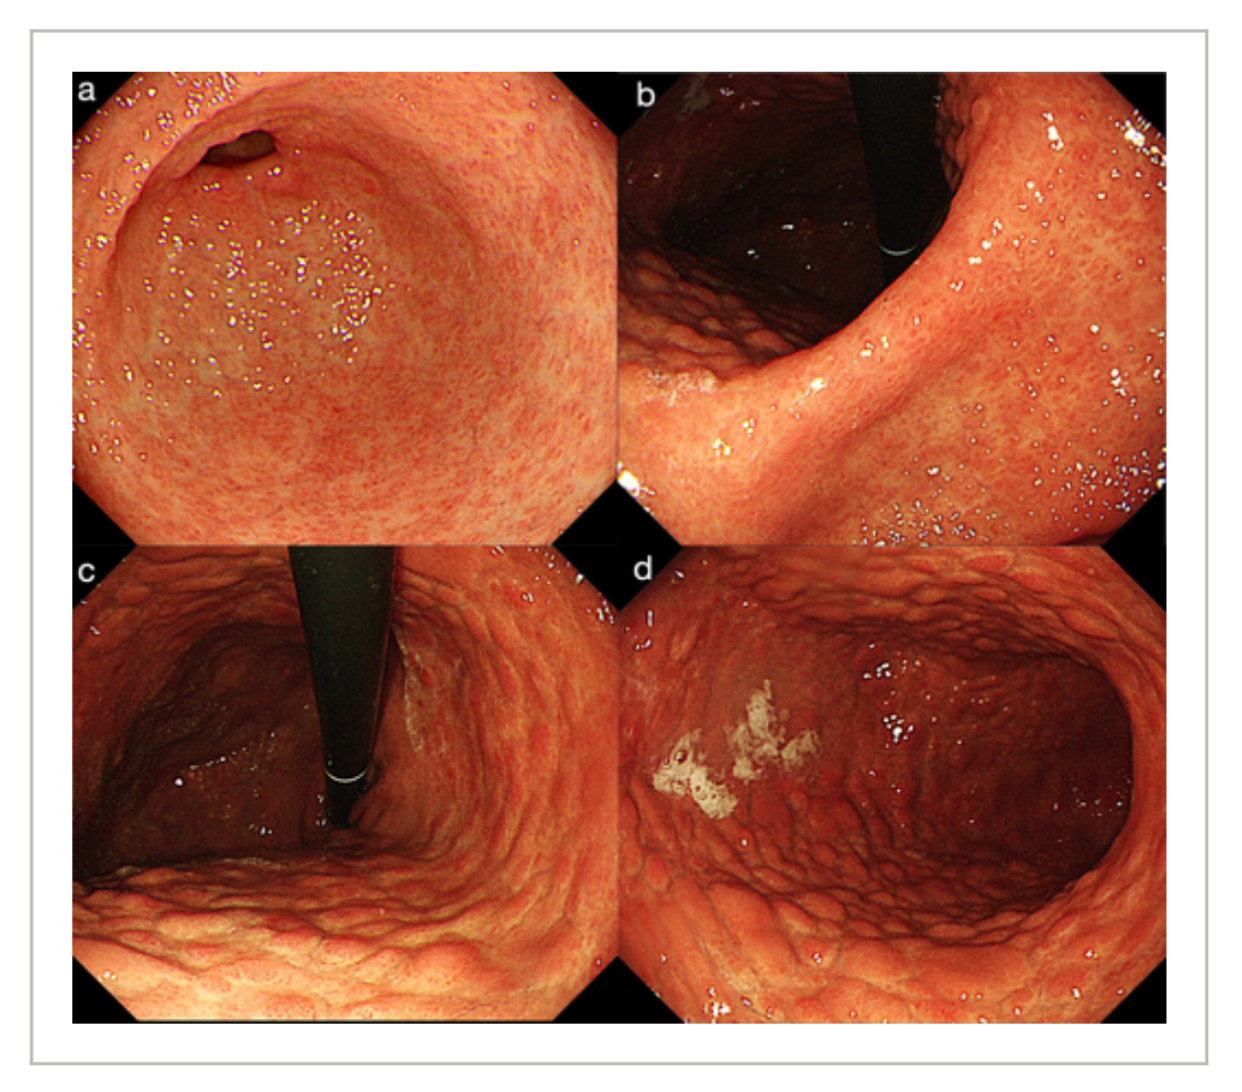

Upper endoscopy revealed diffuse nodular changes in the gastric body mucosa under white light imaging, characterized by nodules encircled by atrophic-like depressions alongside slightly roughened antral mucosa (Figure 1).

Indigo carmine chromoendoscopy highlighted a distinctive “salmon roe-like” nodular pattern in the antrum, where magnified endoscopy demonstrated fragmented microvasculature with uniformly sized vessels arranged in an irregular mesh-like pattern and indistinct or absent microsurface architecture (Figure 2).